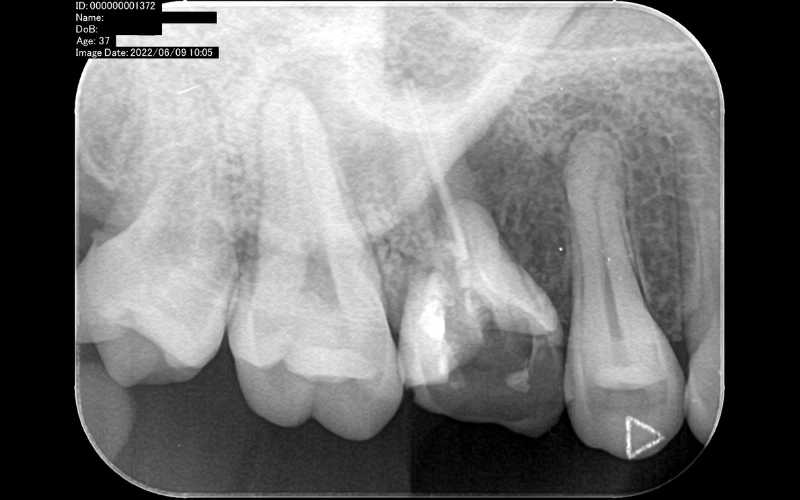

Trong trường hợp khác, khi có trong tay tấm phim nha khoa toàn cảnh của bệnh nhân, “công cụ” này cũng cần đạt đến độ sắc nét nhất định mới có thể bộc lộ được những vấn đề mà bệnh nhân đang gặp phải.

So với phim cận chóp chỉ khu trú từ 3-4 răng, bạn sẽ nhìn rõ những bệnh lý tồn tại ở những chiếc răng đó. Nhưng điều đó không chắc rằng mọi chiếc răng khác đều khỏe mạnh.

Đúng là “khó mà làm dâu thiên hạ”, nhưng sự thật là những điều tiêu cực họ sẽ nhớ lâu hơn là cảm giác thoải mái và dứt cơn đau sau điều trị. Thế nên mới cần đến X-quang toàn hàm! Bởi sau khi bạn có trên tay tấm phim này, những vấn đề của bệnh nhân sẽ được bộc lộ tất thảy. Họ sẽ bị thuyết phục bởi một tấm phim X-quang toàn cảnh sắc nét và chấp nhận điều trị một cách dễ dàng.

Với những ca bệnh phức tạp (chỉnh nha, nhổ răng 8 đặc biệt, cấy ghép,…), bạn sẽ cần đến phim X-quang toàn hàm, ceph, CBCT. Hiện tại có nhiều trung tâm dịch vụ nha sĩ để bạn thuê chụp. Điều này đồng nghĩa với việc bạn sẽ ở thế “bị động”, bởi cần có thời gian để bệnh nhân sắp xếp lịch đi chụp và đợi nhận kết quả từ trung tâm.